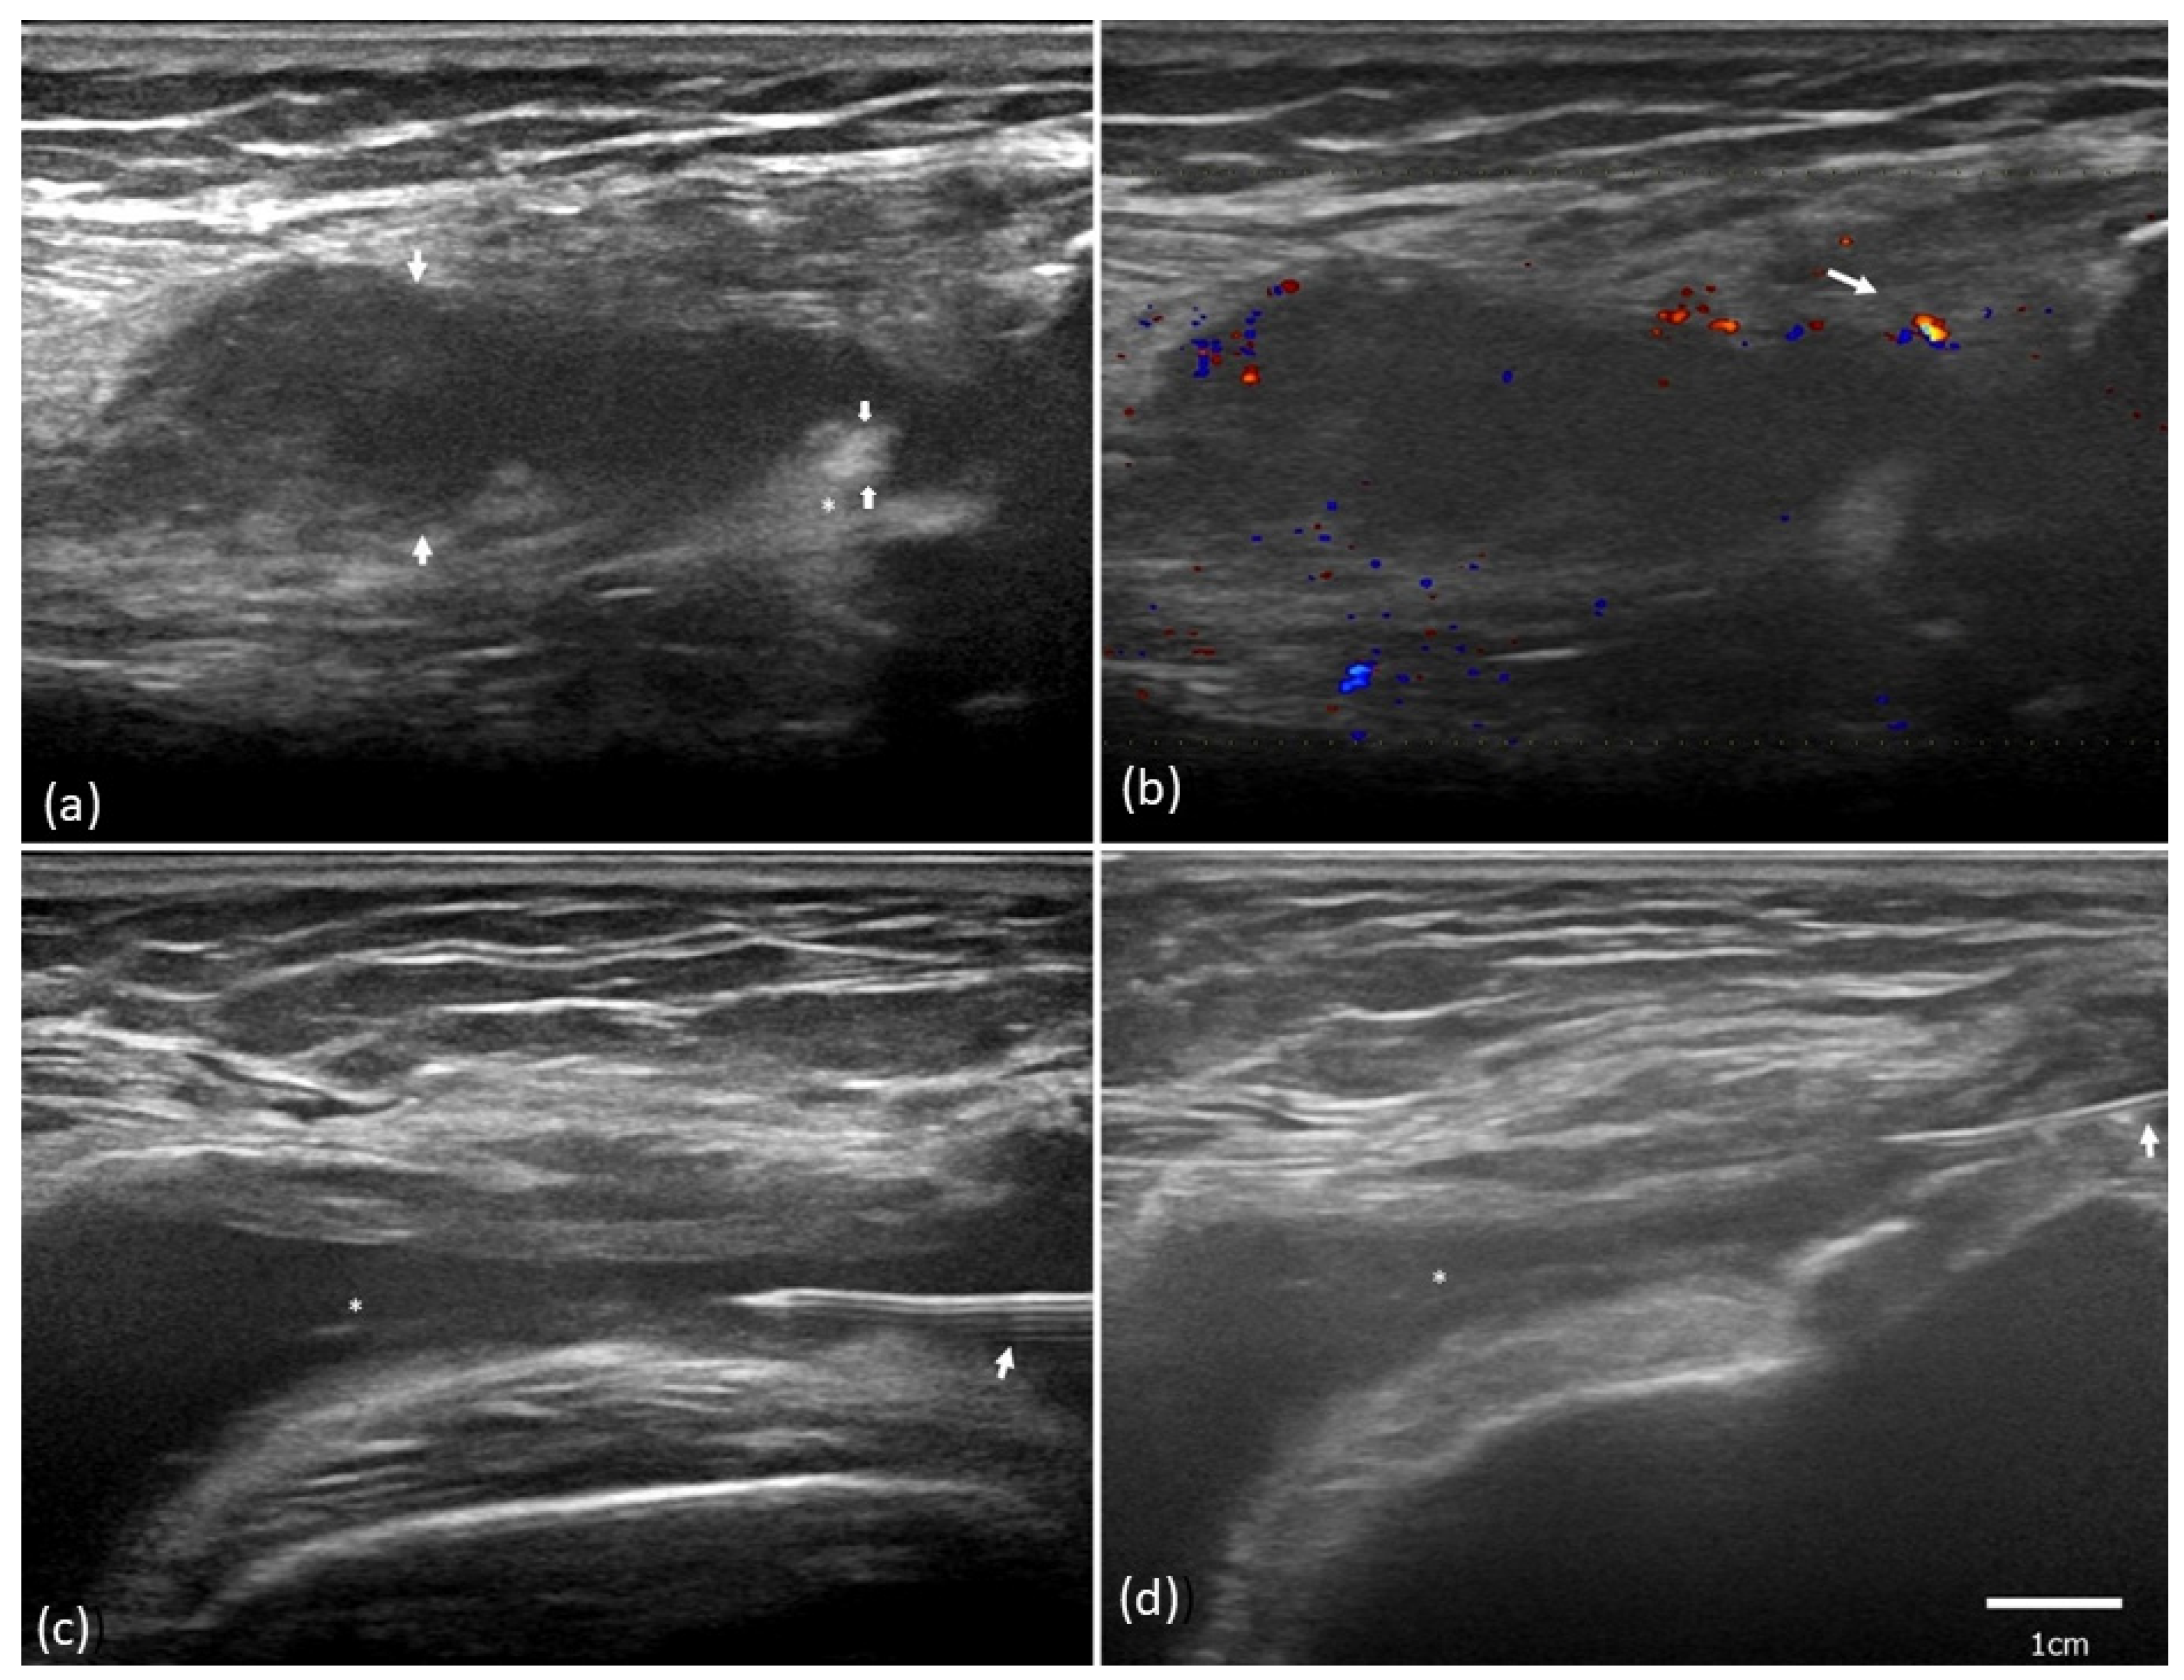

2.2. Ultrasound Synovial Outcome

4.3. Ultrasound Evaluation